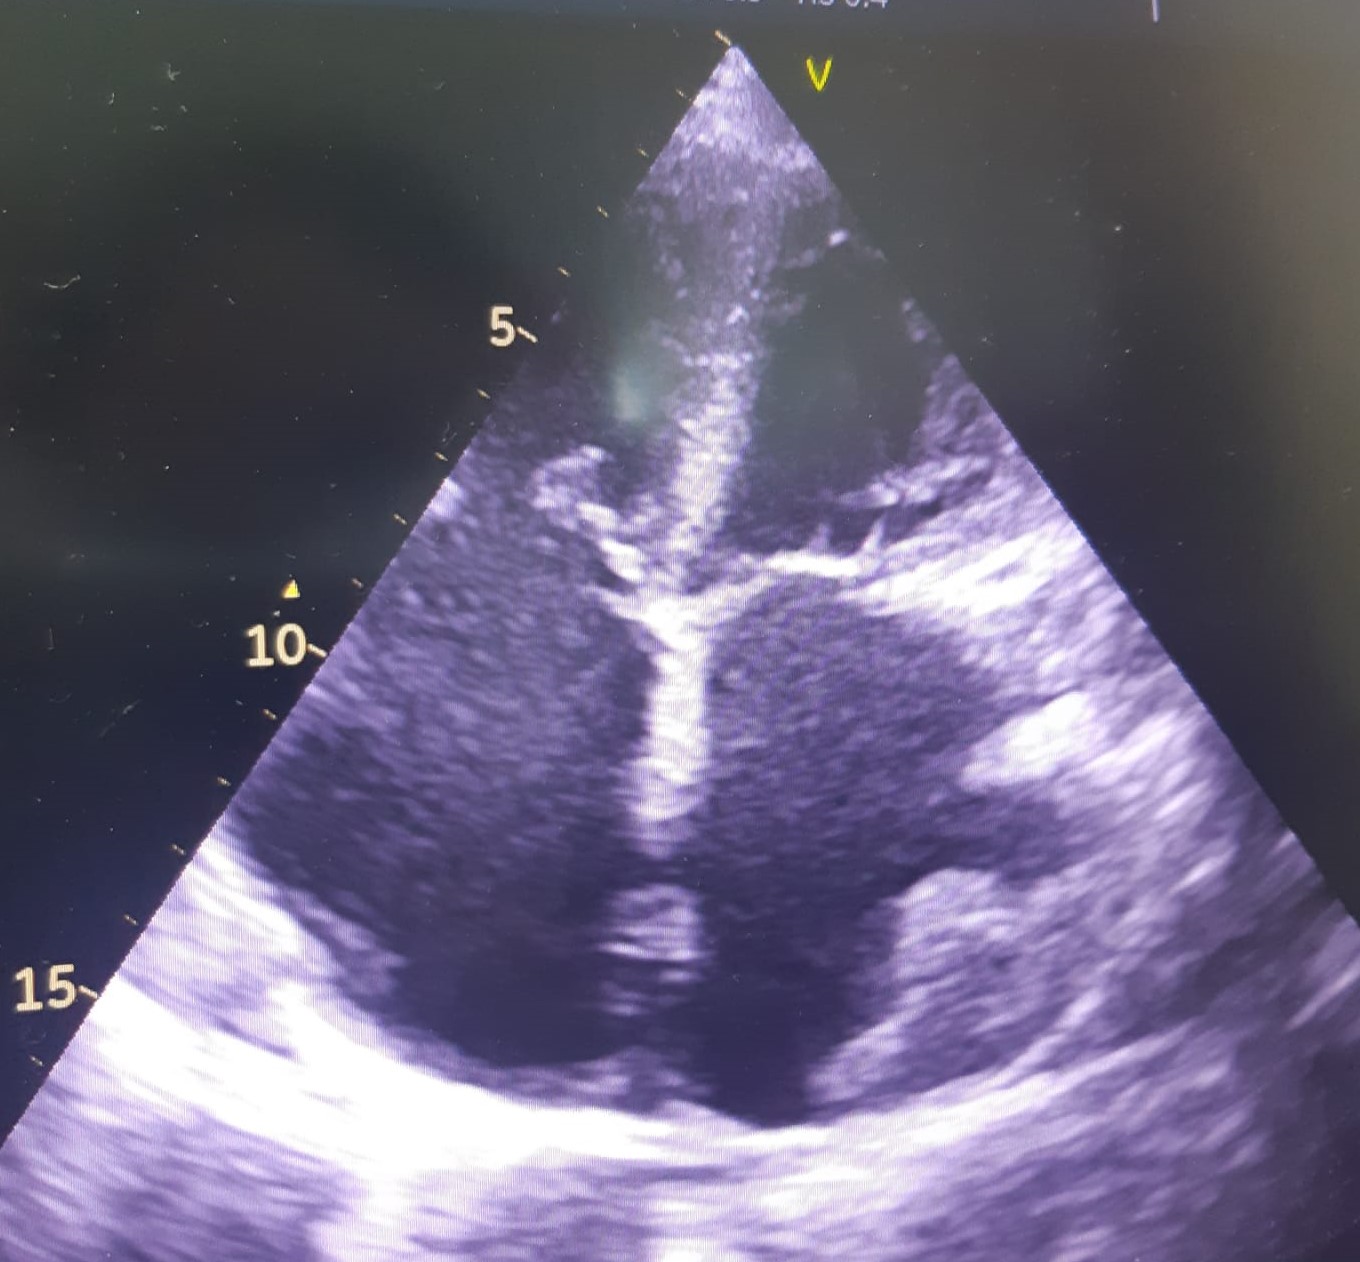

Restrictive cardiomyopathy (RCM) is characterized by non-dilated ventricles, mild or no myocardial hypertrophy with impaired ventricular filling, thus it is defined by abnormal ventricular diastolic function with a normal size LV (see Fig. 8). In the early stages of the disease, the systolic function of the LV is also normal [38].

Fig. 8.The echocardiographic aspect of RCM in an elderly patient presenting with signs and symptoms of heart failure. Apical 4 chamber view showing severe biatrial enlargement, with left atrial thrombus and non-dilated left and right ventricles.